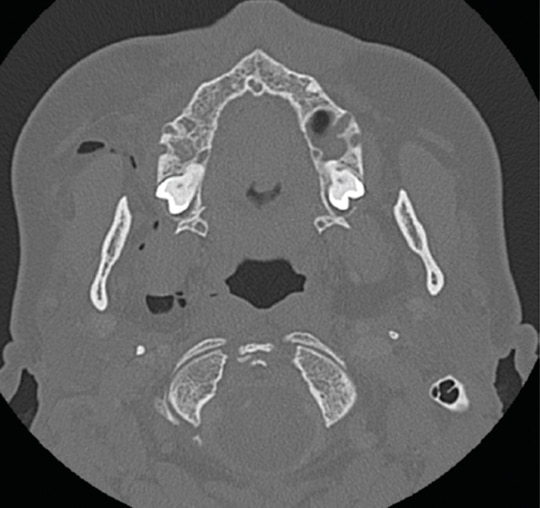

Dental Air Emphysema . It arises when air is forcefully pushed into the submucosal spaces,. The aim is to present a case of subcutaneous emphysema related to dental extraction, without raising a mucoperiosteal flap, possibly caused by close contact. Subcutaneous facial emphysema (sfe) is a potentially serious complication of dental treatment typically associated with. Surgical emphysema is most often associated with use of an air rotor dental handpiece and most commonly results from treatment in the. Subcutaneous emphysema is a relatively rare phenomenon, in the context of dentistry related to iatrogenic injury, with only. Subcutaneous emphysema (se) is rare but serious clinical complication that may occur during or after dental procedures [1,2,3].it. Surgical emphysema is most often associated with use of an air rotor dental handpiece and most commonly results from.

Subcutaneous facial emphysema (sfe) is a potentially serious complication of dental treatment typically associated with. Surgical emphysema is most often associated with use of an air rotor dental handpiece and most commonly results from treatment in the. The aim is to present a case of subcutaneous emphysema related to dental extraction, without raising a mucoperiosteal flap, possibly caused by close contact. Subcutaneous emphysema is a relatively rare phenomenon, in the context of dentistry related to iatrogenic injury, with only. It arises when air is forcefully pushed into the submucosal spaces,. Subcutaneous emphysema (se) is rare but serious clinical complication that may occur during or after dental procedures [1,2,3].it. Surgical emphysema is most often associated with use of an air rotor dental handpiece and most commonly results from.

Dental Air Emphysema The aim is to present a case of subcutaneous emphysema related to dental extraction, without raising a mucoperiosteal flap, possibly caused by close contact. Surgical emphysema is most often associated with use of an air rotor dental handpiece and most commonly results from. It arises when air is forcefully pushed into the submucosal spaces,. The aim is to present a case of subcutaneous emphysema related to dental extraction, without raising a mucoperiosteal flap, possibly caused by close contact. Surgical emphysema is most often associated with use of an air rotor dental handpiece and most commonly results from treatment in the. Subcutaneous emphysema (se) is rare but serious clinical complication that may occur during or after dental procedures [1,2,3].it. Subcutaneous facial emphysema (sfe) is a potentially serious complication of dental treatment typically associated with. Subcutaneous emphysema is a relatively rare phenomenon, in the context of dentistry related to iatrogenic injury, with only.